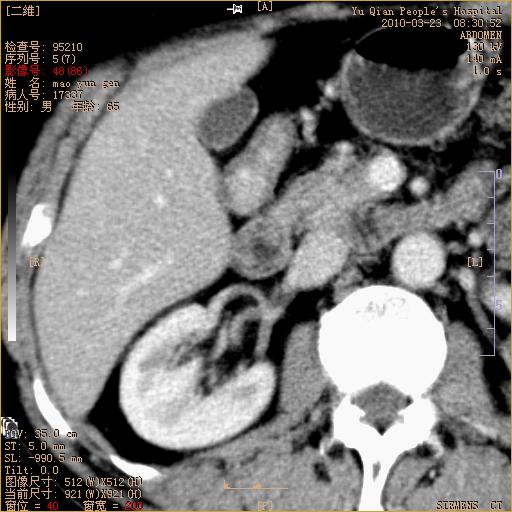

标题: CT25266:消瘦月余,前来肝部检查,请看看肠腔 [打印本页]

标题: CT25266:消瘦月余,前来肝部检查,请看看肠腔

肝区结肠占位,腺癌可考虑,建议肠镜活检。

升结肠肠壁增厚,不均强化,考虑升结肠腺癌可能性,建议肠镜检查。

1)考虑升结肠癌。2)右肾小囊肿。